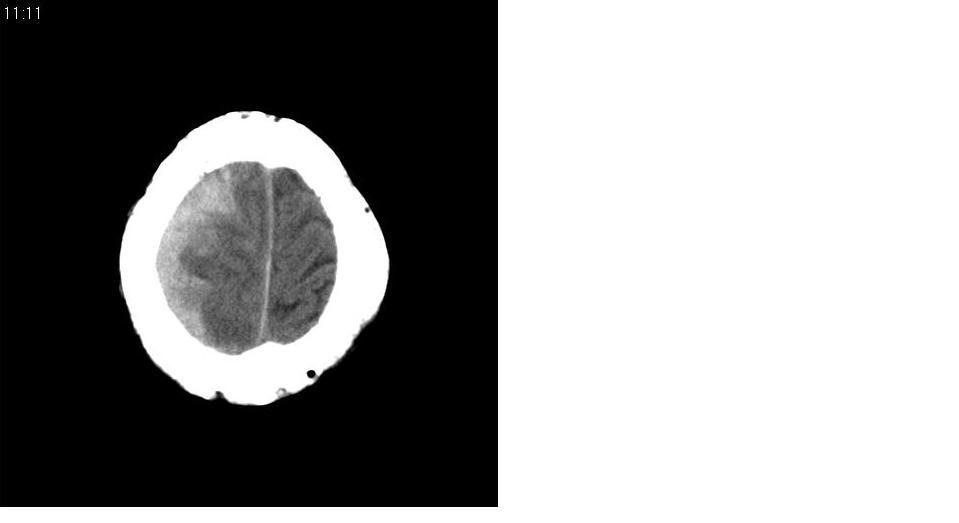

以下是引用川北影像在2007-8-14 15:33:00的发言:[br]1、右侧颞叶脑挫裂伤伴血肿形成。[br]2、右侧额颞顶部硬膜下血肿伴大脑廉下疝形成。

以下是引用gaoshengjiang在2007-8-14 16:30:00的发言:[br]大家都认为右侧颞叶脑挫裂伤伴血肿形成;右侧额颞顶部硬膜下血肿伴大脑廉下疝形成;蛛网膜下腔出血。 但硬膜下血肿、脑内血肿量不多,而大脑廉下疝明显,右侧颞叶类圆形高密度灶,周围轻度水肿,呈蟹足状,考虑脑内占位所致脑内血肿、突然晕倒、硬膜下血肿、颞叶脑挫裂伤等一系列改变。[br][br] [br]

以下是引用拾荒者在2007-8-14 21:59:00的发言:[br][quote]以下是引用gaoshengjiang在2007-8-14 16:30:00的发言:[br]大家都认为右侧颞叶脑挫裂伤伴血肿形成;右侧额颞顶部硬膜下血肿伴大脑廉下疝形成;蛛网膜下腔出血。 但硬膜下血肿、脑内血肿量不多,而大脑廉下疝明显,右侧颞叶类圆形高密度灶,周围轻度水肿,呈蟹足状,考虑脑内占位所致脑内血肿、突然晕倒、硬膜下血肿、颞叶脑挫裂伤等一系列改变。[br][br] [br]